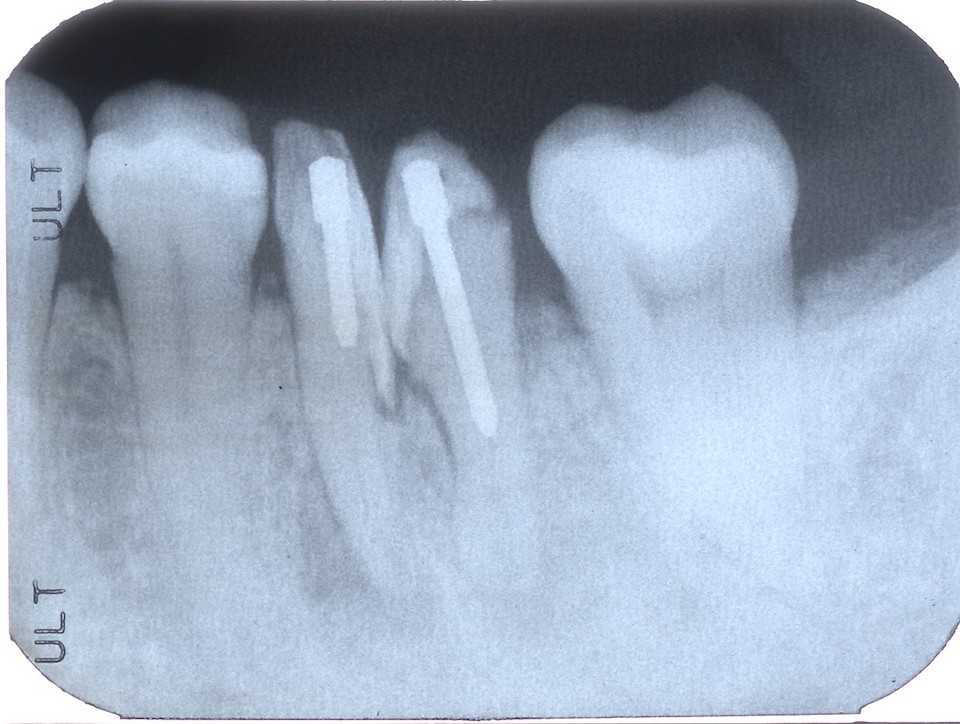

40台女性、左下6、Per、外傷性クラック

GAができていたので歯髄を開けて見たのだが、クラックがあったので3MIX+α-TCPで根管充填したが、GAは消えなかった。やはりクラックが深部まで進んでいるのか?

これ以上の打つ手がないので抜歯再植を試みた。

抜歯も分割抜歯だったがまだ病状が進んでいないので骨植もよかったので、かなり時間もかかり難しかった。

結局クラックは遠心根だけで近心根には見えなかったので、側枝があるのかもしれないが、近心のGAの原因はよく分からなかった。どうなるのか、経過観察が必要だ。

とりあえずレントゲン写真でのbefore/after

before